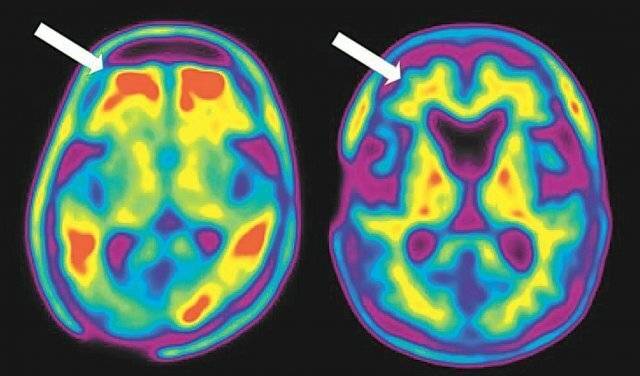

파스칼 겔드세처(Pascal Geldsetzer) 미국 스탠퍼드대 의대 교수 연구진은 3일 국제 학술지 '네이처'에 "영국 웨일스 지역에서 머크(MSD)의 대상포진 백신 '조스타박스(Zostavax)' 주사를 맞은 사람들은 7년 이내 치매 발병률이 미접종자보다 20% 낮았다"고 발표했다.

연구팀은 이 연구에서 영국 웨일스 지역에서 2013년 시행된 대상포진 백신 프로그램으로 백신이 치매 발병에 미치는 영향을 다른 요인들을 배제하고 조사할 수 있는 ‘자연 임상실험’ 환경이 형성된 점에 주목했다.

백신 접종 후 7년간 접종 그룹과 비접종 그룹의 건강을 비교한 결과 접종 그룹의 대상포진 발생률이 37% 감소한 것으로 나타났다.